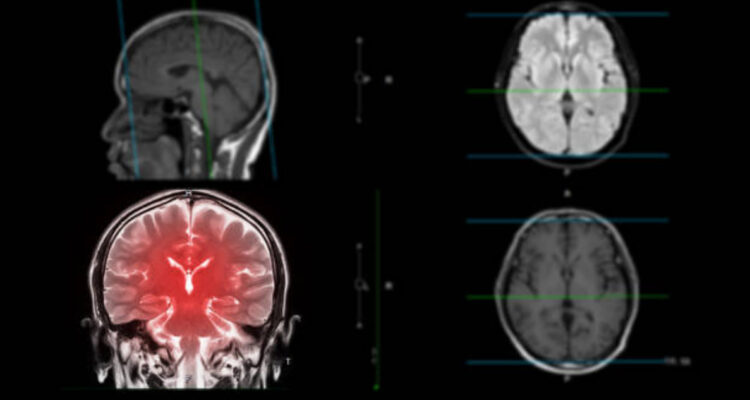

El estudio, realizado en ratones, consiguió regular el contenido de oxígeno y el nivel de pH en tumores. La batería se puede implantar subcutáneamente en la superficie del tumor.

China desarrolló una batería implantable que puede eliminar y detener el crecimiento de tumores